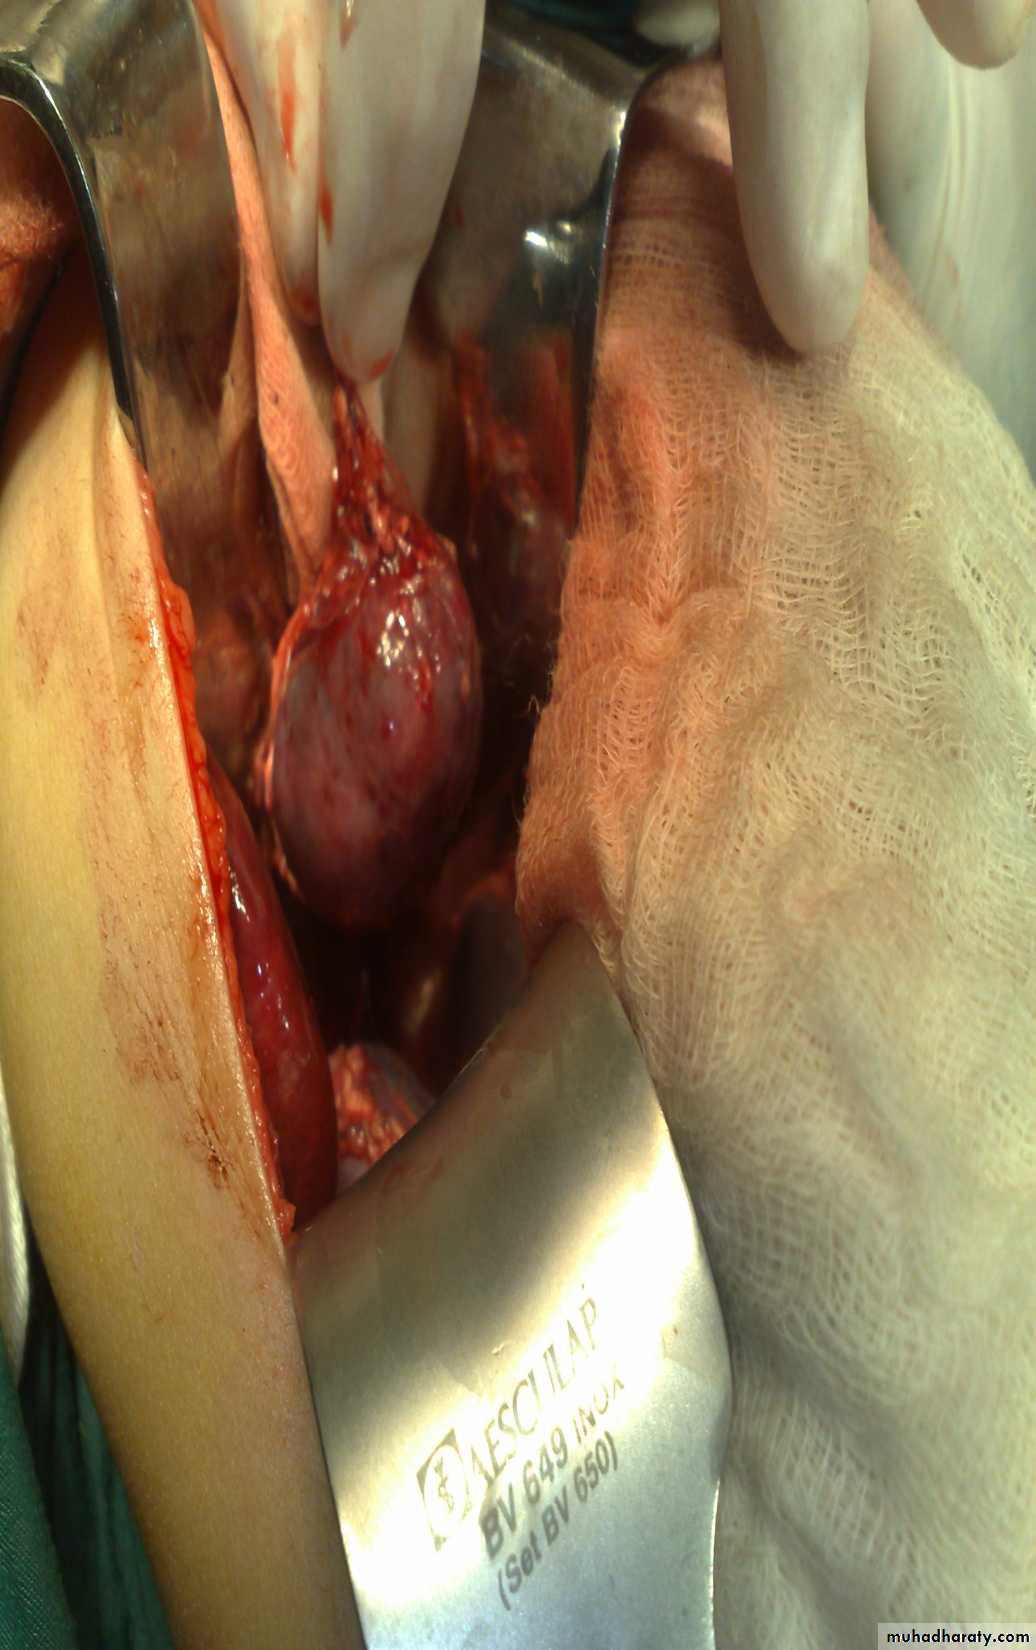

The Child with an Abdominal Mass